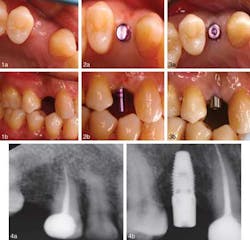

CASE 1Patient 1.Figure 1. Occlusal and lateral view before the procedure. Figure 2. Occlusal and lateral view of the direction indicator placed during the surgery showing minimal bleeding. Figure 3. (a) Occlusal view of the healing abutment in place immediately after implant insertion. (b). Lateral view of the direction indicator placed during the surgery. Figure 4. Digital periapical radiographic view before and after implant placement.